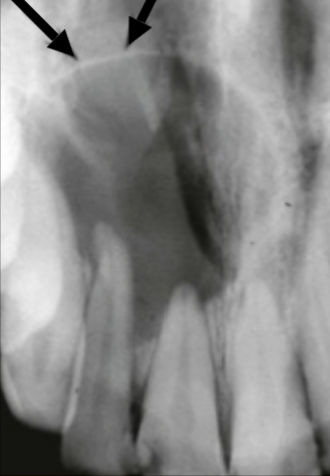

Describe this Radicular Cyst

Epicenter at apex (usually evidence of dental disease or trauma)

Well-defined, corticated

Lucent

Circular

Resorption, Displacement, Expansion (effect on adjacent structures)

Why is this Radicular cyst less circular/oval in this case?